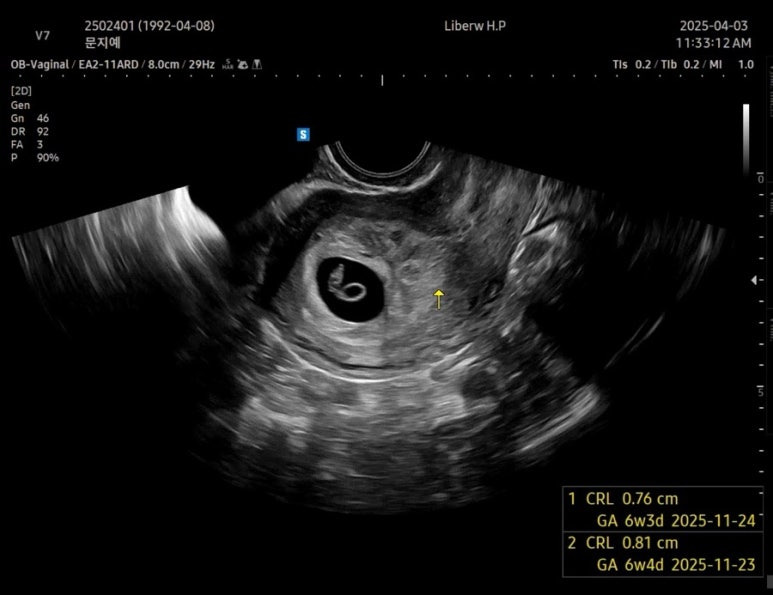

2일만에 쑥쑥커서 0.76cm가 된 사탕이🍬

장비가 좋아서 그런지 초음파가 엄청 선명하다!

드디어 6주 !!!!

예정일은 11월 24일로 변경

차뇨리랑 같이 들은 사탕이 심장소리

튼튼하게 잘 뛰고 있었다

심장박동수는 136bpm